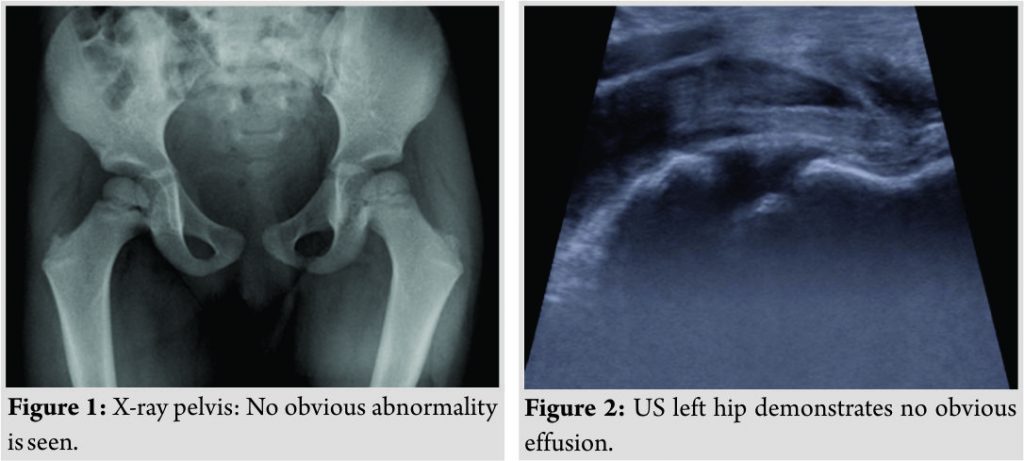

Initial laboratory studies revealed normal renal function (estimated glomerular filtration rate >90), elevated C-reactive protein (CRP) of 77, erythrocyte sedimentation rate (ESR) of 76,white cell count (WCC) of 9.3, and neutrophils of 5.0. Inflammatory markers deteriorated further during her admission with a maximum CRP of 125 and ESR of 80. Peripheral blood cultures were taken, which indicated no growth after 48h, with no causative pathogen isolated after extended culture. Pelvic X-ray and a left knee X-ray were performed to rule out any bony abnormality, and both were normal (Fig. 1). An ultrasound scan of the hips suggested a very small left-sided effusion (Fig. 2). The patient then underwent MRI abdomen and pelvis revealing approximately 1.5 × 0.9 (axial) × 4.5 cm (craniocaudal) collection, between the left iliac blade and overlying iliacus muscle, which was noted to be swollen and edematous. Inflammatory changes also tracked inferiorly into the groin (Fig. 3a-c).It was concluded that this was likely pyomyositis centered on the left iliacus muscle with a small collection.

An unwell child with a limp, in the absence of trauma, can usually be attributed to a few common differential diagnoses, such as transient synovitis, septic arthritis, or osteomyelitis. This reinforces the importance of extrapolating a concise history and knowledge of focal findings on examination. Our patient had a history of a viral illness, which preceded the onset of the limp, which may lead the clinician to think of transient synovitis. However, due to the systemic features present, this was unlikely. The Kocher criteria highlight four parameters that indicate the probability of septic arthritis (non-weight bearing, temperature >38, ESR > 40, and WCC >12). Our patient had 3 out of 4 of these and so the preliminary diagnosis of septic arthritis was made [9]. With normal X-rays and an insignificant hip effusion on ultrasound, osteomyelitis was considered. Following consultant orthopaedic and radiologist discussion, urgent MRI was indicated to rule out osteomyelitis and to look for other potential pathology, before any joint aspiration or washout [10].

On the basis of possible septic arthritis, the patient was commenced on IV antibiotics according to trust antimicrobial guidelines (flucloxacillin 5 mg/kg). She was consented for the left hip aspiration ± proceed to open washout. On review the following morning, she was hemodynamically stable and had been apyrexial since admission. The decision was made to proceed with an ultrasound scan first before possible aspiration (Fig. 2). With the MRI findings to hand and following discussion with the pediatric surgeons, it was felt that the collection did not require surgical intervention (Fig. 3a-c). She continued with IV antibiotics until both her pain and inflammatory markers reduced significantly, and on further liaison with microbiology, she was stepped down to oral antibiotics (flucloxacillin 250 mg/5 ml), which she responded to although exact pathogen was not identified. An oral antibiotic course of a period of 3 weeks was to be completed on discharge, with outpatient follow-up arrangements.